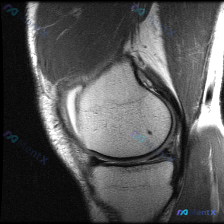

今天遇到一个很有代表性的情况:用户提供了一张膝关节矢状位MRI,主诉提示「半月板异常」,但我们阅片后发现结果和预期完全不一样,整理出来给大家讨论。 基本影像信息 这是一张膝关节矢状位质子密度或T2加权MRI,图像清晰度良好,信噪比适中,没有明显运动伪影,解剖结构显示清晰,层面大致位于膝关节中部区域。...

刚整理了一份膝关节MRI读片病例,分享一下完整分析思路。 病例影像基本信息 这是一张膝关节MRI矢状位图像,用户提问是否存在半月板异常,我们来一步步分析: 影像基础评估结果 1. 骨骼与关节: 股骨远端、胫骨近端皮质连续,无明显骨折,无明显骨髓水肿、软骨下囊肿,关节间隙和对合关系基本正常 2. 关节...